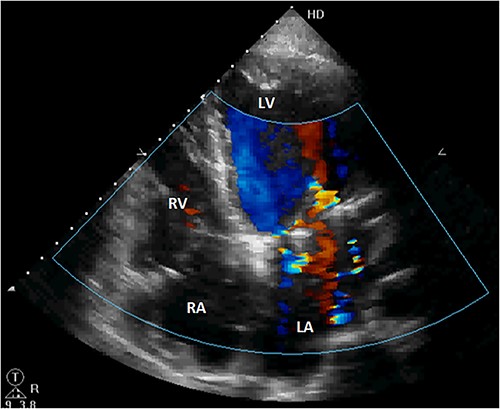

Initial physical examination showed stable vital signs. Auscultation found systolic murmurs of mitral and tricuspid regurgitations. There were no peripheral edema or other signs of heart failure. Abdominal examination revealed no tenderness, hepatomegaly or ascites. Electrocardiogram at admission showed sinus rhythm with no conduction abnormalities or signs of ischemia. Chest radiograph found an enlargement of the cardiac silhouette. Routine blood tests were normal. Transthoracic echocardiography (TTE) found a bi-atrial cystic structure, which we initially suspected to be a hydatid cyst as cystic echinococcosis is highly endemic in Morocco. Color Doppler showed a massive shunt with blood coming into the right atrium (RA) from an unknown source (Fig. 1). Cardiac magnetic resonance imaging (CMR) showed a bilobed cystic lesion hypointense on T1 and T2 sequences, with the same signal as cardiac chambers, located below and behind the left atrium (LA). The superior lobe was 48-mm wide and the inferior lobe 65-mm wide. On the peripheral wall of this structure, a giant circumflex artery (LCX), with a right atrial shunt, was present (Fig. 2). Coronary angiography (CA) along with computed tomography angiography (CCTA) confirmed the bilobed circumflex saccular aneurysm and CAF (Figs 3 and 4).

Initial TTE. (A) Parasternal short-axis view showing a bi-atrial cystic lesion; (B) apical 4-chamber view showing color Doppler aliasing in the RA, indicating a shunt. RV, right ventricle; LV, left ventricle; C, cystic lesion.